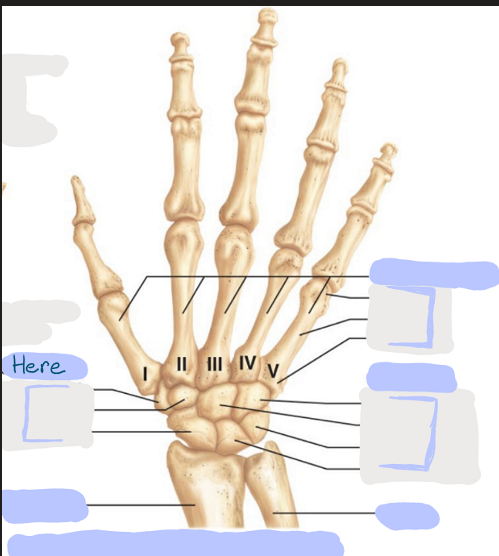

What is this picture of?

Anterior View of the Right Hand

What is here?

Where is the Ulna?

What is here?

Where is the Radius?

What is here?

Where are some of the Carpals?

What is here?

Where are some of the Carpals?

What is here?

Where are the Phalanges?